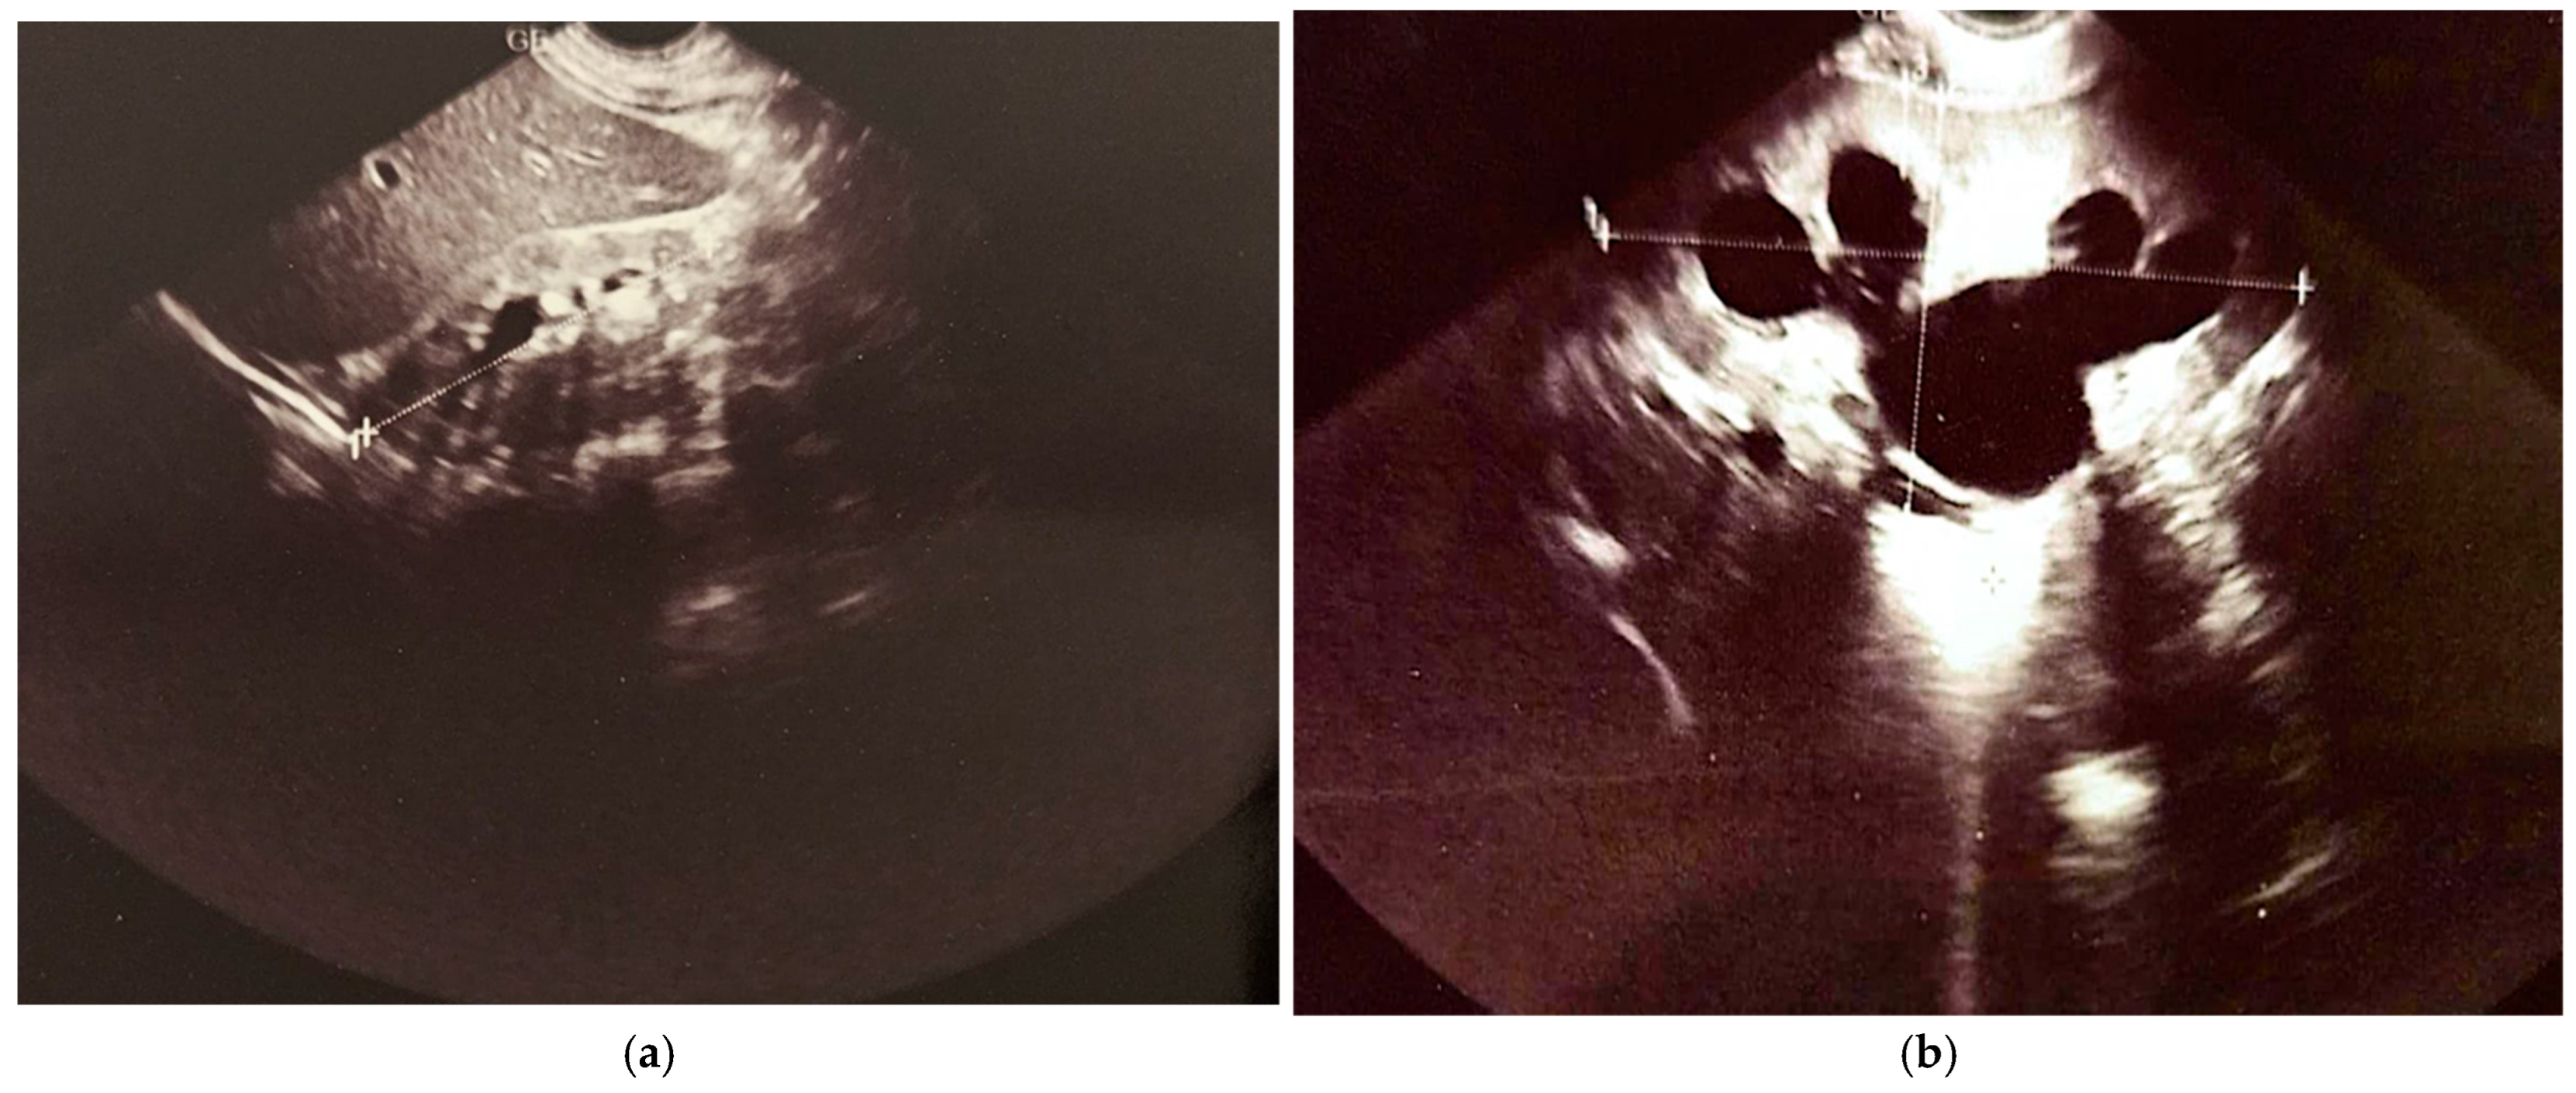

The first cystography was performed at 1 month and 20 days of life (Figure 3a, imaging on the left side). Findings: bilateral ureterostomy. Bladder in normal position, reduced in size, with smooth but slightly lobulated contours, and homogeneously opacified. Passive and active vesicoureteral reflux on the left side.

Figure 3.

Cistography evaluation at two time points. (a) At 1 month and 20 days (b) At 1 year, 4 months, and 25 days (2 months post-surgery).

At 1 year, 4 months, and 25 days of life, voiding cystourethrography was performed at 2 months distances from the surgery. The second cystography was showing an irregular, pseudo-diverticular contour of the urinary bladder and a thickened bladder neck. No vesicoureteral reflux or post-void residual urine was identified (Figure 3b, imaging on the right side).